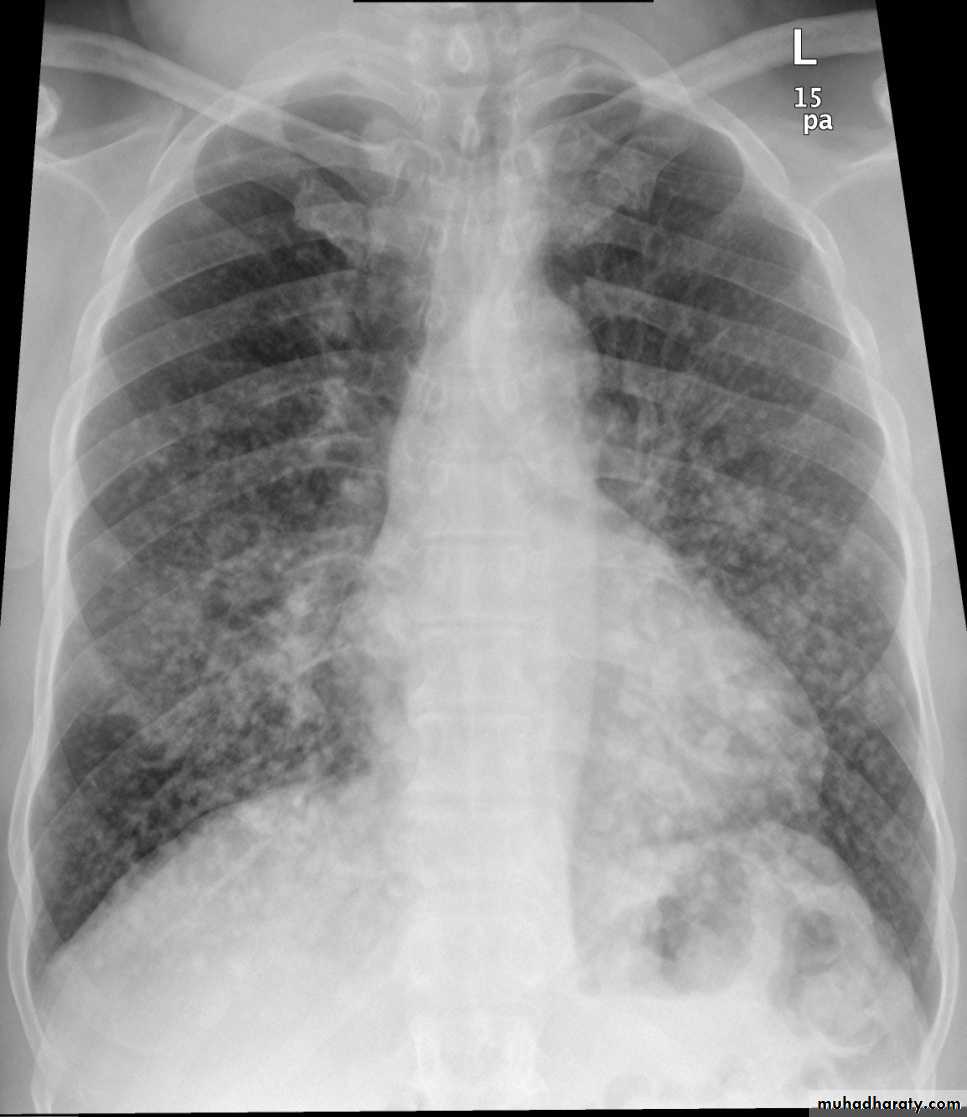

4. Miliary tuberculosis is uncommon but carries a poor prognosis. It represents haematogenous dissemination of an uncontrolled tuberculous infection. It is seen both in primary and post-primary tuberculosis. Although implants are seen throughout the body, the lungs are usually the easiest location to the image. Miliary deposits appear as 1-3 mm diameter nodules . are uniform in size and uniformly distributed